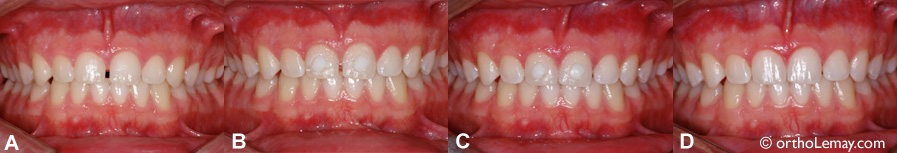

Fermeture d’espaces et de diastèmes

Parfois la fermeture d’un diastème peut être assez simple.

• (A) Patient ayant une excellente occlusion et bon alignement général des dents. Il désirait fermer l’espace entre les centrales supérieures qu’il trouvait inesthétique.

• (B) La correction fut faite à l’aide d’attaches de la couleur des dents et d’un élastique permanent transparent qui rapproche les dents. Le tout est pratiquement invisible.

• (C) Après 10 jours l’espace est fermé et les centrales se touchent. Les attaches peuvent alors être enlevées.

• (D) Une fois la correction terminée, il est nécessaire de coller une attelle de rétention sur la face interne des dents afin de prévenir l’ouverture de l’espace à nouveau.